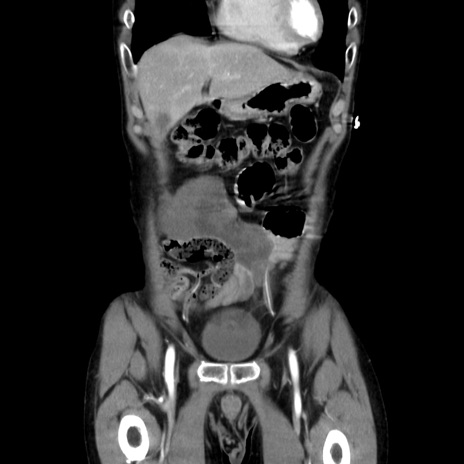

症例37(冠状断像)

【症例】40歳代 男性

【主訴】腹痛

【現病歴】4時間ほど前に電車に乗車中に臍部上より腹痛出現。徐々に増悪し起立困難となり、救急外来受診。生ものは数日食べていない。今朝お雑煮を食べた。

【身体所見】BT 36.8℃、BP 117/84mmHg、HR 91/min、SpO2 97%、苦悶様、腹部:臍上部広範囲圧痛あり、反跳痛±

【データ】WBC 8100、CRP 0.03